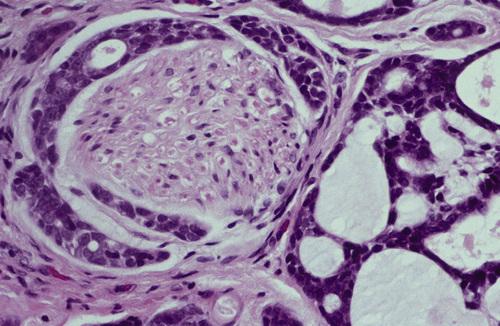

Low-power view showing a well-circumscribed, encapsulated tumor mass. Even at this power, the mixture of glandular epithelium and myoepithelial cells is evident.

pleomorphic adenoma

These plasmacytoid myoepithelial cells are rounded and demonstrate an eccentric nucleus and eosinophilic hyalinized cytoplasm, thus resembling plasma cells.

pleomorphic adenoma

Ductal structures (left) with associated myxomatous background (right) produced from extensive accumulation of mucoid material between myoepithelial tumor cells.

pleomorphic adenoma

Chondroid material (right) with adjacent ductal epithelium and myoepithelial cells. The chondroid appearance results from vacuolar degeneration of tumor cells.

pleomorphic adenoma

Many of the ducts and myoepithelial cells are surrounded by a hyalinized, eosinophilic background alteration. At times, fat or osteoid also is seen.

pleomorphic adenoma